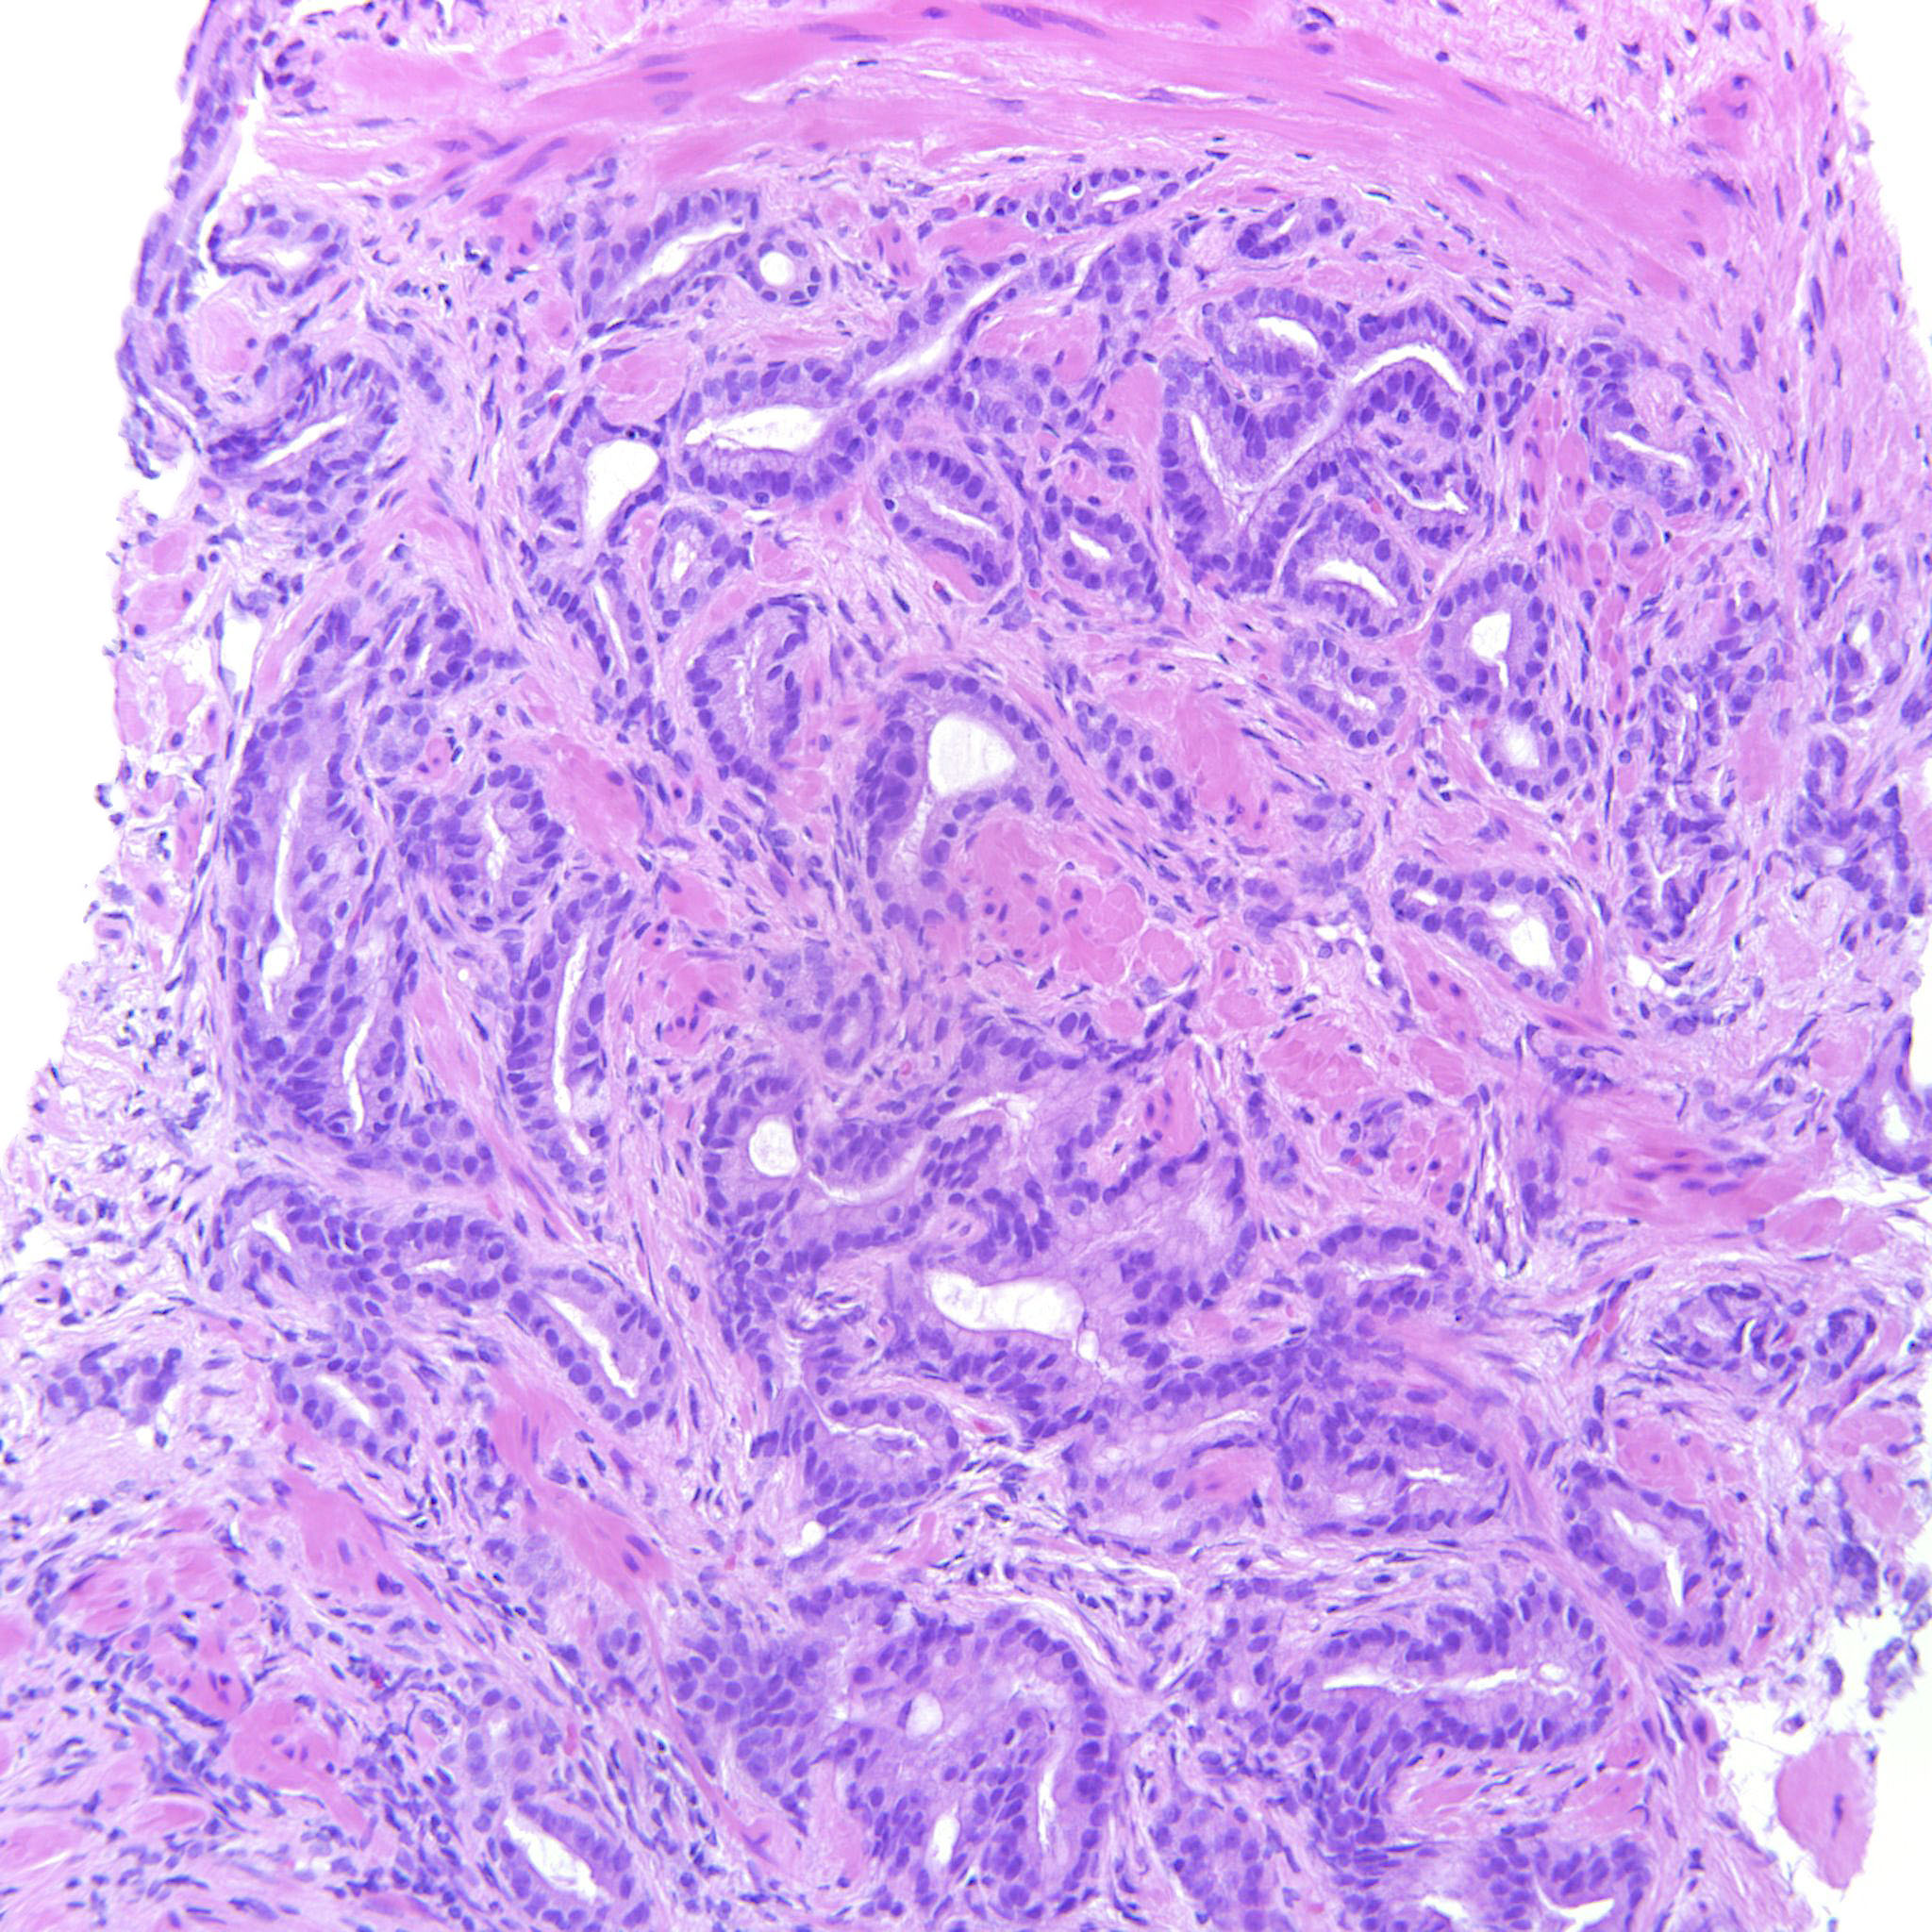

Prostate cancer grading

Case ID: 516